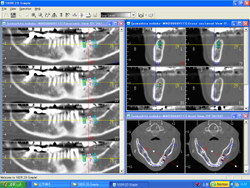

当院では、インプラント手術を安全で確実に行うため、CT画像解析をしています。

顎の骨の厚さや強さをCT検査で解析し、インプラントを植立する位置を コンピューターシュミレーションして決定します。

当院では、インプラント手術を安全で確実に行うため、CT画像解析をしています。

顎の骨の厚さや強さをCT検査で解析し、インプラントを植立する位置を コンピューターシュミレーションして決定します。

CT画像